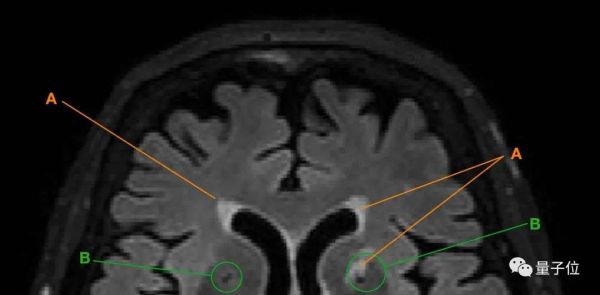

得出以上结论,研究人员主要是通过追踪老人大脑中脑白质高信号(WMH)和腔隙的变化来实现的。

△A为脑白质高信号;B为腔隙

以上两种现象都是脑小血管病(CSVD)的主要表现。

这种疾病在老年人群体中高发,会表现出情感障碍、认知功能下降等症状,

也就是说,当老人的大脑中出现脑白质高信号、腔隙变多变大等情况,就意味着老人的大脑可能在发生退化。